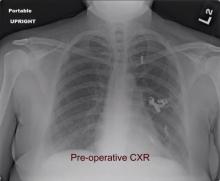

Thoracoscopic Left Upper Lobectomy for Refractory Pulmonary Arteriovenous Malformation [1]

Pulmonary arteriovenous malformations (PAVM) can have potentially serious neurological and cardiac consequences if left untreated. Embolization has supplanted surgical resection as the first line treatment modality. However, this technique is not always successful and carries risks of air embolism, migration of the coil, myocardial rupture, vascular injury, pulmonary hypertension, and pulmonary infarction. The author presents a case of persistent hemoptysis from a left upper lobe PAVM, despite multiple embolizations. The patient, a 38-year-old female with Osler-Weber-Rendu syndrome, underwent a thoracoscopic left upper lobectomy with complete resolution of her symptoms. She was discharged home on day three to take care of her ten children.